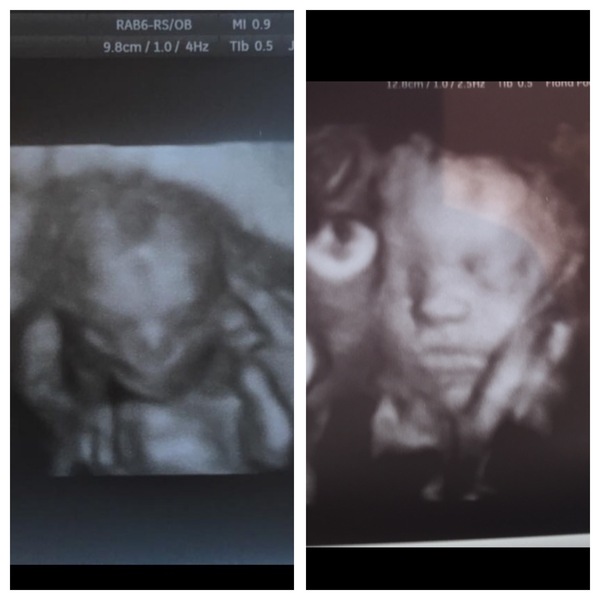

Big diff from 16/30 so 4mths to 7.5

Just got back from my clinic in Riga (where I got my IUI) and also decided for an ultrasound there. My DH was with me and asked my dad to come along (don't have mum anymore). The scan (equivalent to 20w NHS anomaly scan) was so thorough and got so many photos including a 3D image. Suffice to say my little one is developing well! And she was so active and gave us High Five! Loved it! Dad was in such an awe and emotional! Bless him! My 20w with NHS is on the 31st, will still go for it. It's so nice to see her every time there's a scan! Oh and I bought a pram while there, much cheaper! And saved £300 on a pram alone (3-in-1 combination).

Blondes your DD is looking like a real baby now! I guess it's mostly just growth now and organ maturation. Exciting. You have also made me want to make lists and pack bags now Grin

Blondes wow!! What a clear picture!!

Blondes the hospital is just a bit run down and everyone so disorganised. My consultant seems to be half asleep every time I see her. I'm going to start looking at others next week but worried I've left it all a bit late. Your 4d scans are amazing by the way - such a moving thing to see, your story is very touching too.